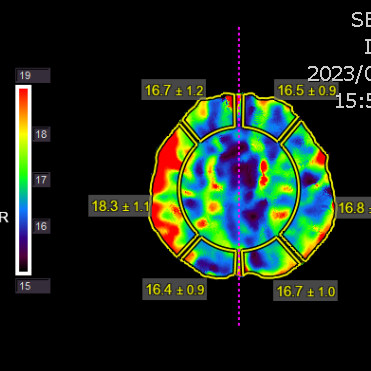

右侧相对低灌注

灌注明显改善,支持进一步随访

复查脑灌注相对缺血比术后1.5个月有加重

灌注比术前进一步改善